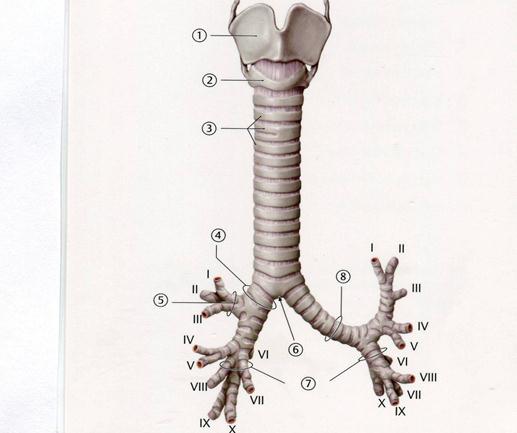

56. Төменде көрсетілген суреттегі белгіленген № 6 анатомиялық құрылымды атаңыз.

А.Басты бронхтар

В.Жүзіктәрізді шеміршек

+++++С.Кеңірдек айырығы

D.Қалқанша шеміршек

Е.Үлестік бронхтар

80.Травматологиялық бөлімшеге тыныс алу жолдарына бөгде зат түскен жарақаттанған науқас әкелінді.Бронхтардың анатомиялық ерекшеліктерін ескере отырып, бөгде заттың қандай бронхқа көп жағдайда өтуі мүмкін?

А++.Оң жақ басты бронхқа

B. Сол жақ басты бронхқа

C. Сегментерлы бронхқа

D. Соңғы бронхиолаларға

E. Тынс алу бронхиолаларға

85. Науқаста қабыну процессі салдарынан кеңірдектің артқы қабырғасы зақымдалды. Қабыну процессі қандай мүшеге өтуі мүмкін?

А. Айырша безге

B. Жұтқыншаққа

C. Көмекейге

D. Қалқанша безіне

E++.Өңешке

89. Науқаста ас түйіршігінің өңештен өтуіне кедергі туады. Рентгендік тексеріс кезінде,

Ү кеуде омыртқасының деңгейінде астың өңештен өтпеуі анықталды. Өңештің осы бөлігінде ас түиіршігінің өтуіне қай мүшенің ісігі кедергі жасайды?

А. Айырша бездің

B. Жұтқыншақтың

C. Көмекейдің

++D. Кеңірдектің

E. Қалқанша безінің